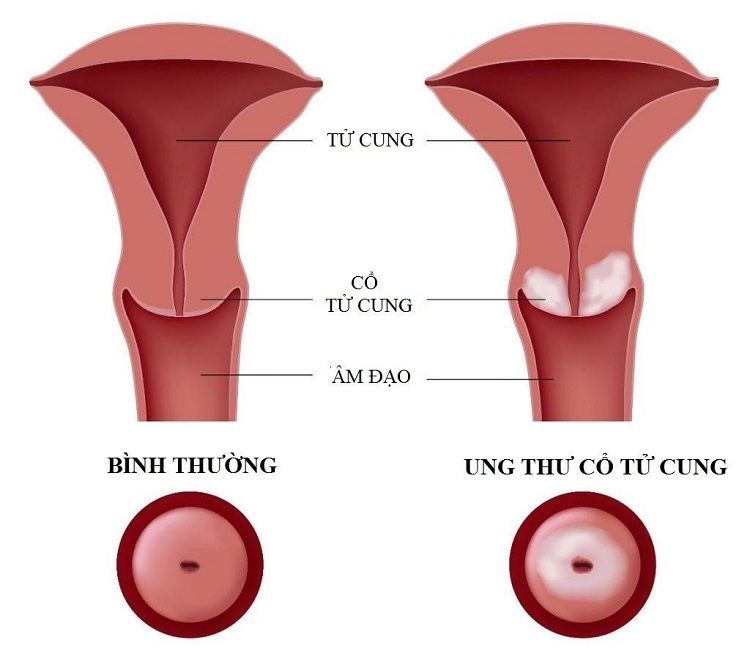

Vaccine HPV 👩🦰 – Phòng ngừa ung thư cổ tử cung và điều bạn cần biết

Ung thư cổ tử cung là một trong những bệnh ung thư phổ biến và [...]